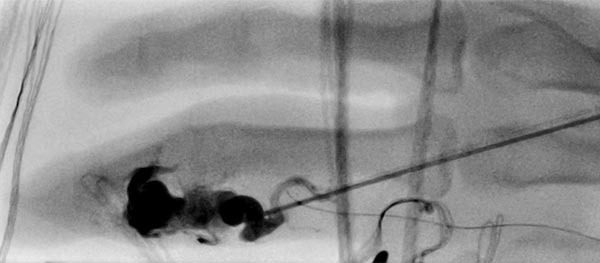

Fluoroskopische Abschlußkontrolle nach erfolgreicher Nidusembolisation der AVM. Der transarteriell von brachial eingebrachte Mikrokatheter wurde während der perkutanen Embolisation als Landmarke für die zuführende Arteria digitalis propria belassen. Zusätzlich sichtbar röntgendichte Markierungen durch auf der Haut aufliegende Kompressen.

Fluoroskopische Darstellung des Cast nach erfolgreicher Nidusembolisation der AVM. Zur besseren Orientierung für die Operationsplanung erfolgt diese Darstellung auch noch einmal ohne Subtraktion mit sichtbaren Knochen.